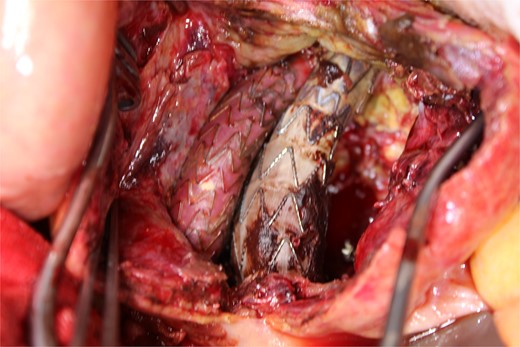

A photo taken from the cranial side of the patient. A jet of bleeding was identified from a lumbar artery.

A photo taken from the caudal side of the patient. No endoleaks other than the type II endoleak were observed.

This time, he was brought to the emergency department with a chief complaint of abdominal pain. His medical history includes Stage 4–5 chronic kidney disease (CKD), with an estimated glomerular filtration rate (eGFR) of approximately 15 mL/min/1.73 m2, secondary to nephrosclerosis and diabetic nephropathy, as well as persistent atrial fibrillation, which was treated with warfarin. Upon admission, laboratory results revealed a hemoglobin level of 6.2 g/dl and a prothrombin time—international normalized ratio (PT-INR) of 6.05. Contrast-enhanced CT demonstrated an AAA measuring 118 × 107 mm, enlarged from 98 × 94 mm 2 months prior, and left retroperitoneal hematoma. IMA and one pair of lumbar arteries were enhanced only in the delayed phase, but blood flow into the aneurysm was not clearly observed (Fig. 1). Given that the landing zones and overlaps of the stent grafts were satisfactory (Fig. 2) and that no type I or type III endoleaks were identified, a ruptured AAA due to TIIEL from the lumbar artery or IMA was highly suspected. We administered 3000 IU/kg of lyophilized human prothrombin complex concentrate in response to the significant prolongation of PT-INR and proceeded with open surgery for ligation of the feeding artery and aneurysmorrhaphy. Intraoperatively, no pulsation was found on the aneurysm. Incision of the aneurysm revealed a large amount of thrombus, which was removed, and then pulsatile bleeding was identified from a lumbar artery (Fig. 3), the ostium of which was sutured from within the aneurysm. This was consistent with the left lumbar artery of the pair enhanced on the preoperative CT and was suspected to be responsible for the rupture. Oozing was also noted from several other lumbar arteries, which were similarly sutured closed. No leak was observed from the proximal or distal ends, nor from the junctions of the stent grafts, and no damage to the stent grafts was observed (Fig. 4). Following this, aneurysmorrhaphy was performed, and the abdomen was closed. The postoperative course was uneventful. A plain CT on postoperative day (POD) 14 showed a reduction in the aneurysm size with no apparent leaks (Fig. 5). The patient was discharged home on POD 24. Although the preoperative eGFR was 8.8 ml/min/1.73 m2, no postoperative deterioration was observed. It gradually improved back to baseline, and dialysis was not required during the follow-up period.